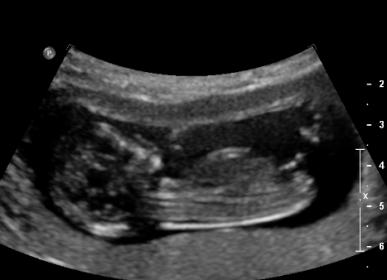

Pls guess girl or boy based on Nubs theory or skull theory?

12 weeks scan.

Heart rate 167